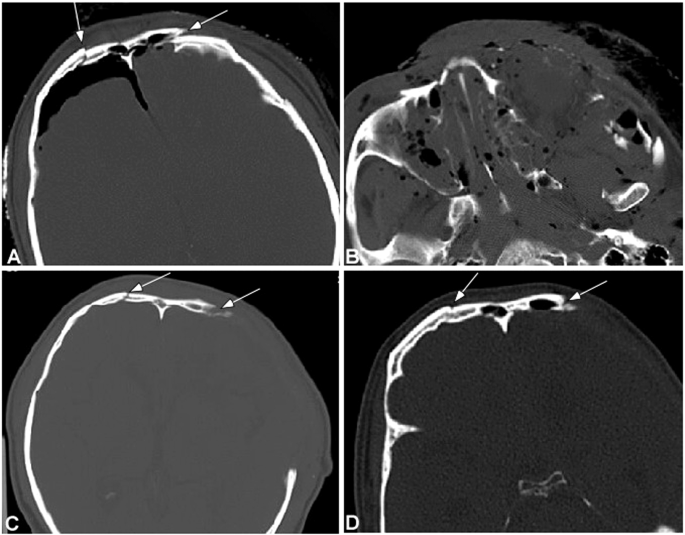

The fracture line was clear and sharp within one week of injury, blunt and sclerosed at the fracture edge 2–3 weeks later, and could be observed over 2 months. Within one to two weeks of injury, obvious swelling existed in adjacent soft tissues, with effusion and mucosal thickening in paranasal sinuses. The effusion in the paranasal sinuses could last a long time. Within three days of injury, air could be observed in the adjacent soft tissues and/or intracranially when the fracture involved the frontal sinus, and the air was completely absorbed after one week. There were 12 cases (28.6%) with intracranial hematomas, but no cases had severe intracranial hemorrhage. Epidural hemoatoma was usually limited in a small area. The absorbing time of hematoma was dependent on the location of hemorrhage, with the subarachnoid hemorrhage usually absorbed completely within one week while epidural hematoma usually over three weeks. In one case with brain contusion and laceration concomitant with intracerebral hemorrhage, the hemorrhage seemed to increase within one week of injury. Five patients (10%) had subdural effusion including one male patient of 68 years of age who had the effusion extended from the left frontal area to both frontal area and both temporal area, and the other four patients were all less than 50 years of age with less and limited epidural effusion. Significant differences (P < 0.05) existed in the changes of signs with time except for those of epidural hematoma, subdural hematoma and epidural effusion (Tables 1 and 2 and Fig. 1).

A male patient of 45 years old had a traffic accident and was diagnosed as having multiple facial fractures, left epidural hematoma, contusion and laceration in the left frontal lobe and left optic nerve injury. (A) On the day of injury, the frontal fracture lines were sharp and clear (arrows) involving bilateral frontal sinus walls with intracranial air collection. (B) Comminuted fractures were shown in the maxillofacial bones with maxillary sinus effusion, air collection in the adjacent soft tissues and swelling of soft tissues. (C) Follow-up scanning two weeks later demonstrated blunt edge of the frontal bone fracture lines (arrows) indicating bone absorption. (D) Three months later, the fracture lines were further blunted (arrow). Bone defect was shown in (C,D) after procedure.